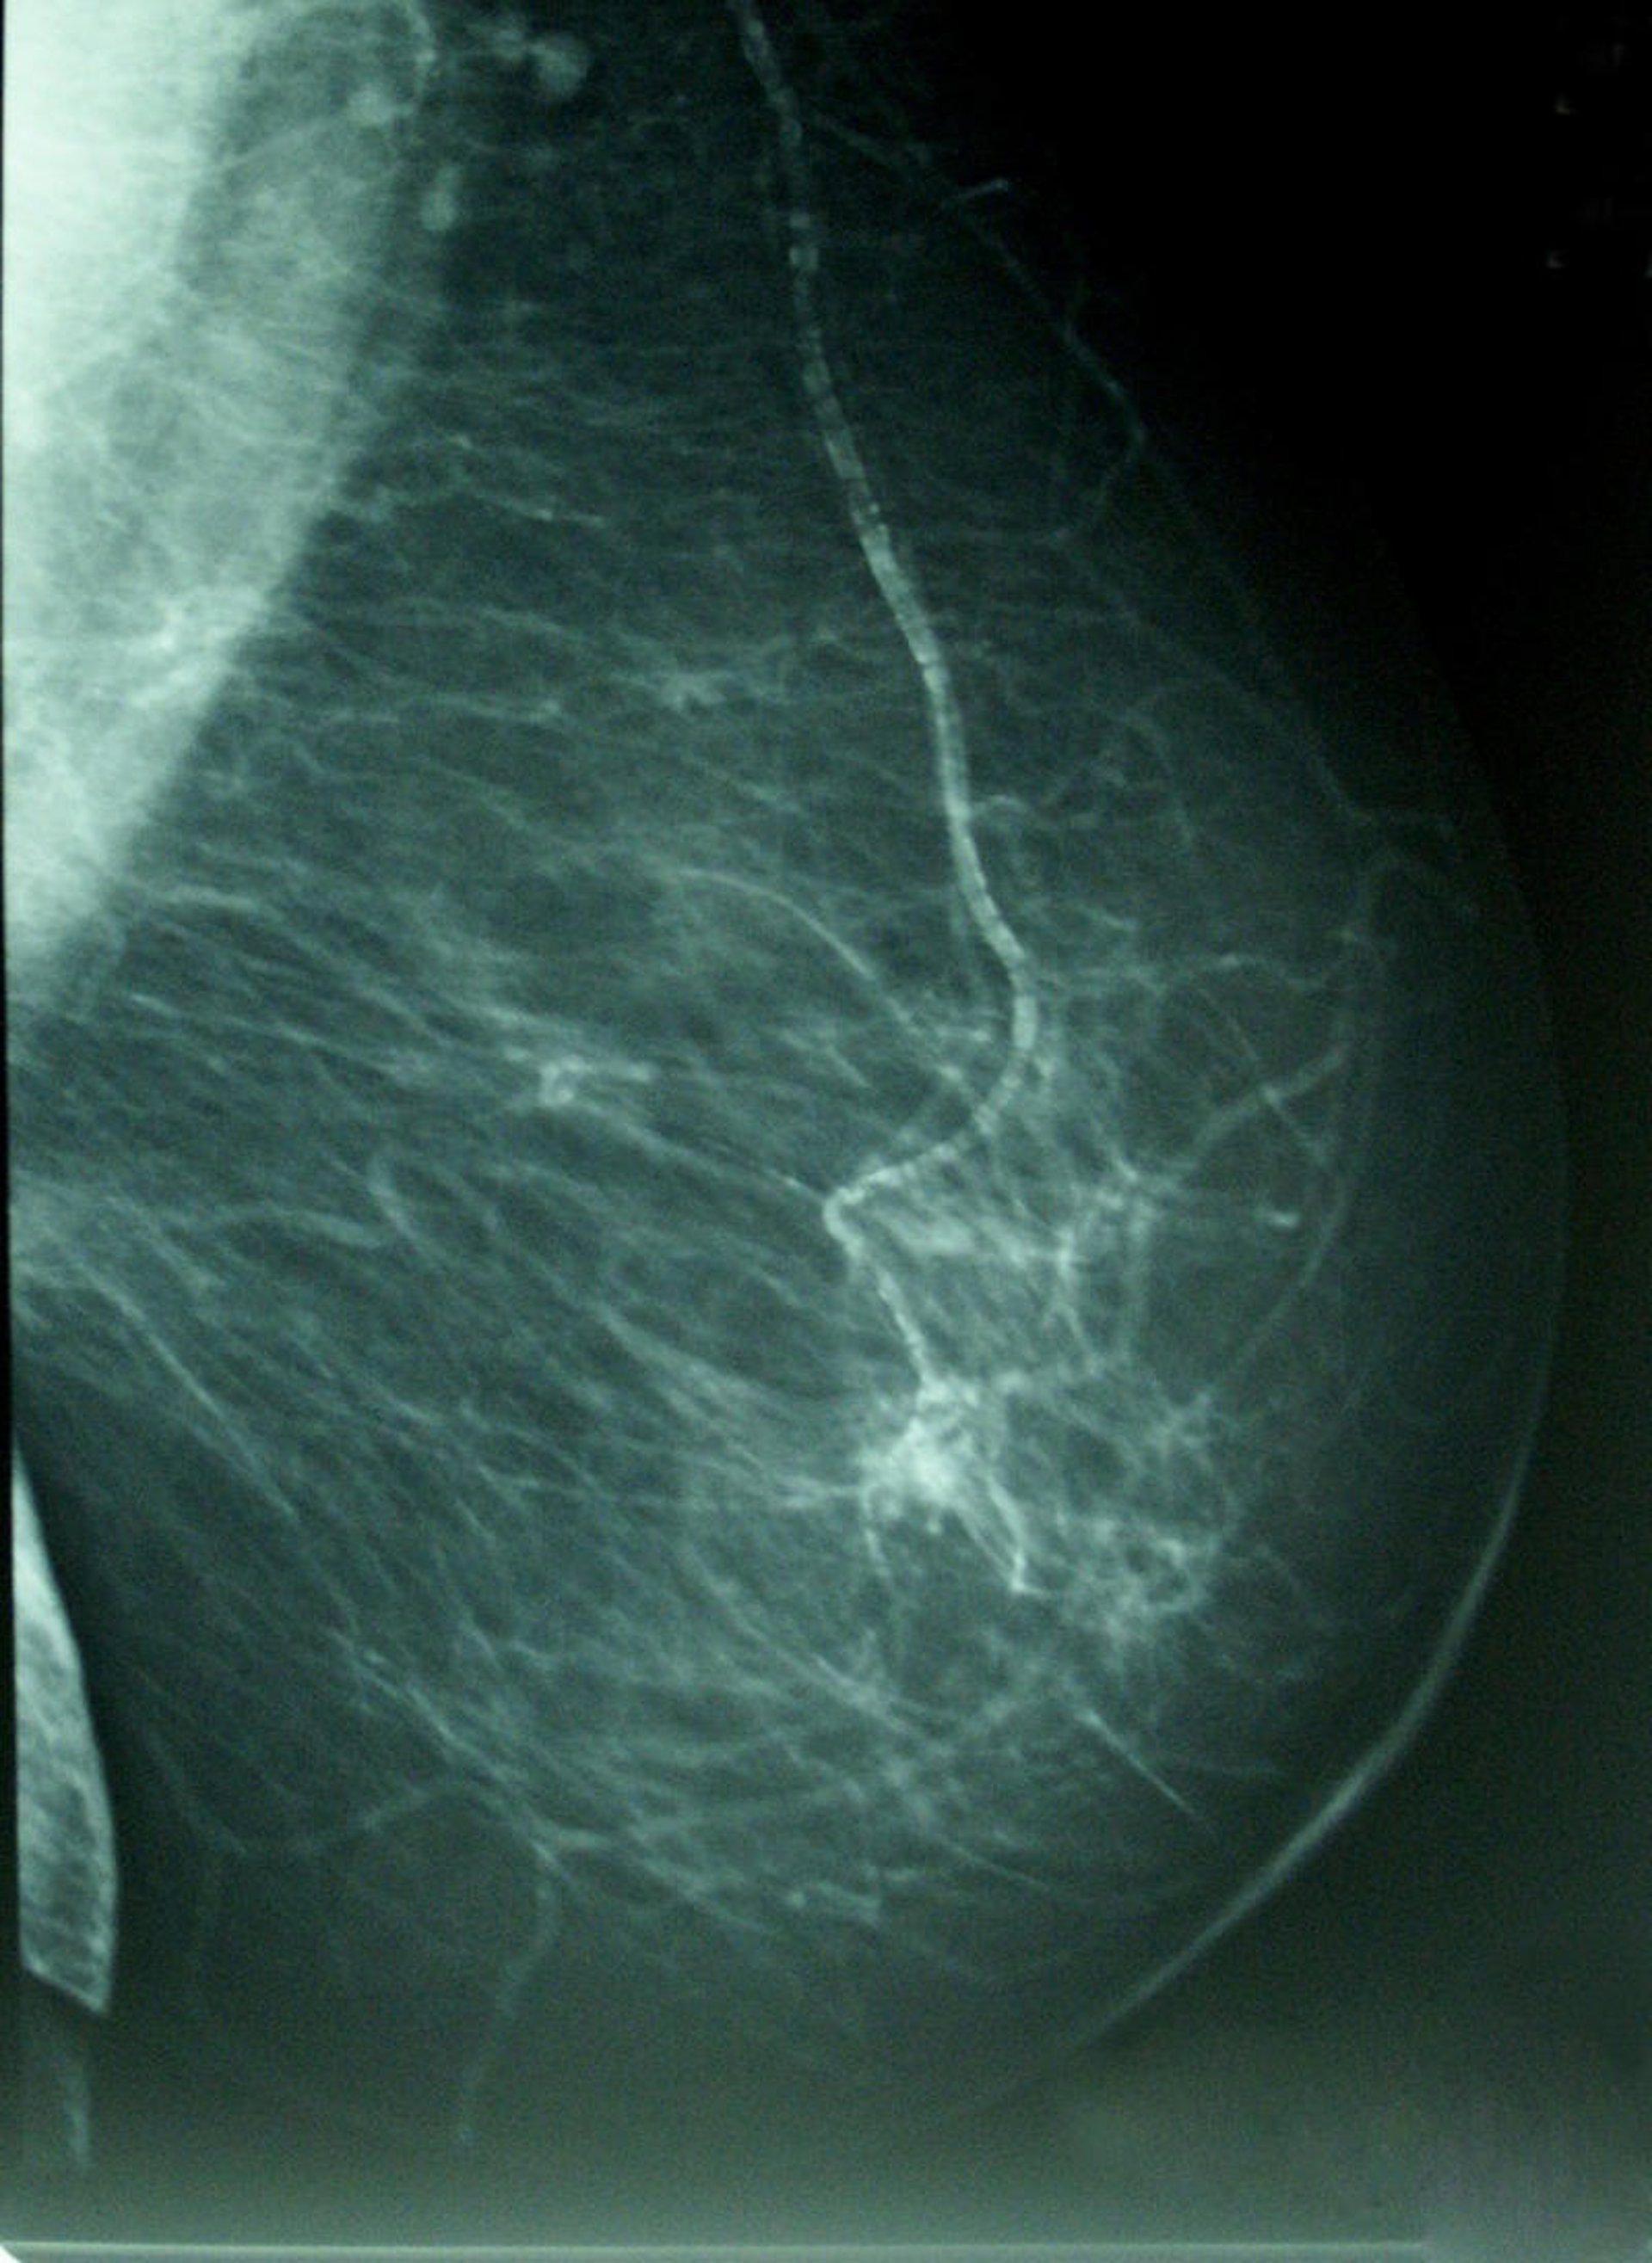

Cáncer De Mama, Densidad Mamográfica